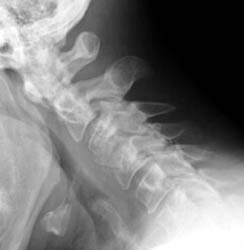

Instability

48 y.o. male with a history of alcohol abuse, depression and degenerative joint disease who is complaining of severe pain in his right neck and shoulder radiating down to his right third and fourth digit. The patient underwent anterior cervical disc fusion. Four months after the initial surgery, the patient still had pain but this time numbness was on flexion mainly and localized to the C5 region.

Lateral flexion and extension radiographs taken 6 months after surgery demonstrate incomplete graft incorporation (delayed healing). Furthermore, with flexion there is anterolisthesis of C4 on C5 (one level below the fusion) by 2-3 mm.